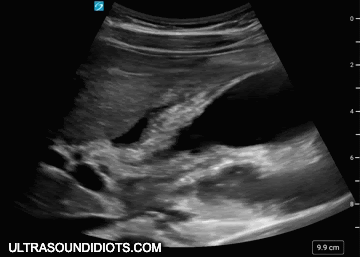

・Nor Adrenalin Release(ノルアドレナリン・リリース)という特殊な微弱超音波を用いて、腕周り、腰回り、ウエスト、ヒップ、背中、太ももなど脂肪の気になる部位のトリートメントを行うことが可能です。